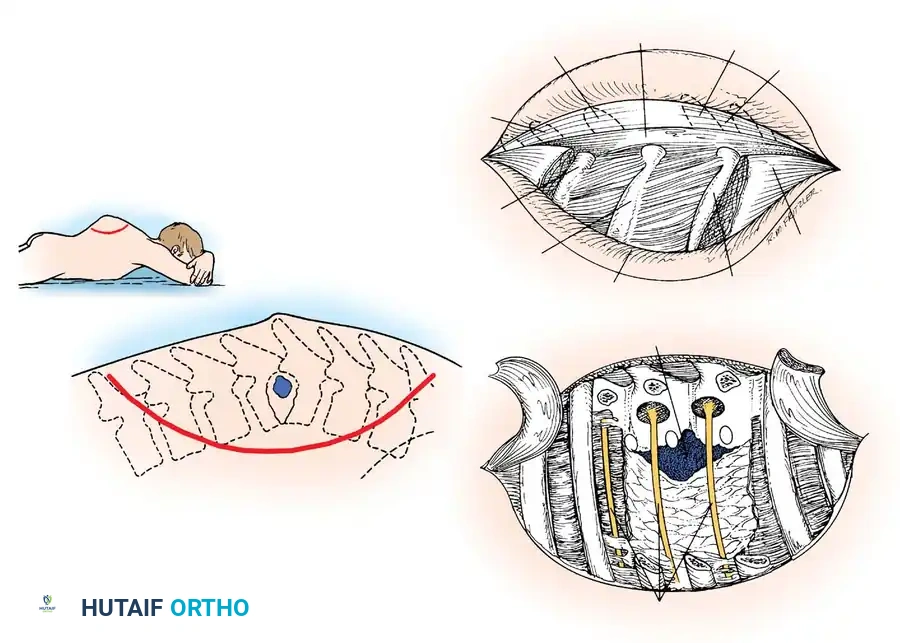

Surgical Steps for the Dorsolateral Approach

- Select the side with the larger paraspinal abscess shadow on preoperative imaging. If symmetric, default to the left side.

- Make a large, curved incision. Begin posteriorly 3.8 cm from the midline and 7.5 cm proximal to the center of the lesion. Curve the incision distally and laterally to a point 12.5 cm from the midline at the apex of the lesion, then curve it back medially to end 3.8 cm from the midline and 7.5 cm distal to the lesion.

- Divide the superficial fascia, deep fascia, and paraspinal musculature down to the ribs. Retract the large myocutaneous flap medially.

- Identify the rib corresponding to the center of the tuberculous focus. You must resect 7.5 to 10 cm of this rib, as well as the ribs immediately proximal and distal to it (three ribs total).

- Free the ribs subperiosteally and divide them with rib shears laterally. Medially, disarticulate and resect the ribs at the tips of the transverse processes.

- Under direct vision, divide the costotransverse ligaments and resect the transverse processes.